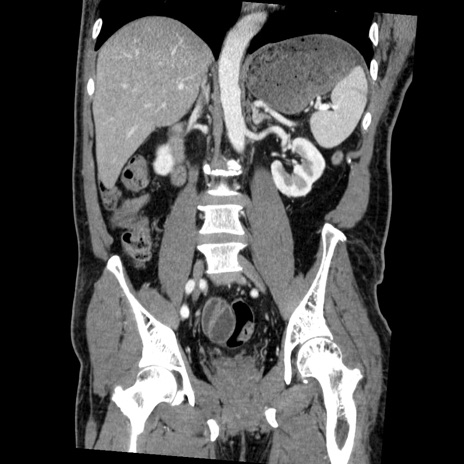

症例22(冠状断像)

【症例】50歳代男性

【主訴】腹痛

【現病歴】AVMからの被殻出血のため回復期リハ病棟入院中。 本日午後3時頃急に下腹部痛が出現した。

【既往歴】AVM、被殻出血、虫垂炎、高血圧

【身体所見】意識晴明、左半身不全麻痺、会話の理解は良好、36.5°C、腹部:膨隆、全体に板状硬、下腹部正中に圧痛点あり、反跳痛-、筋性防御不明、右下腹部にope scar

【データ】WBC 9400、CRP 0.06